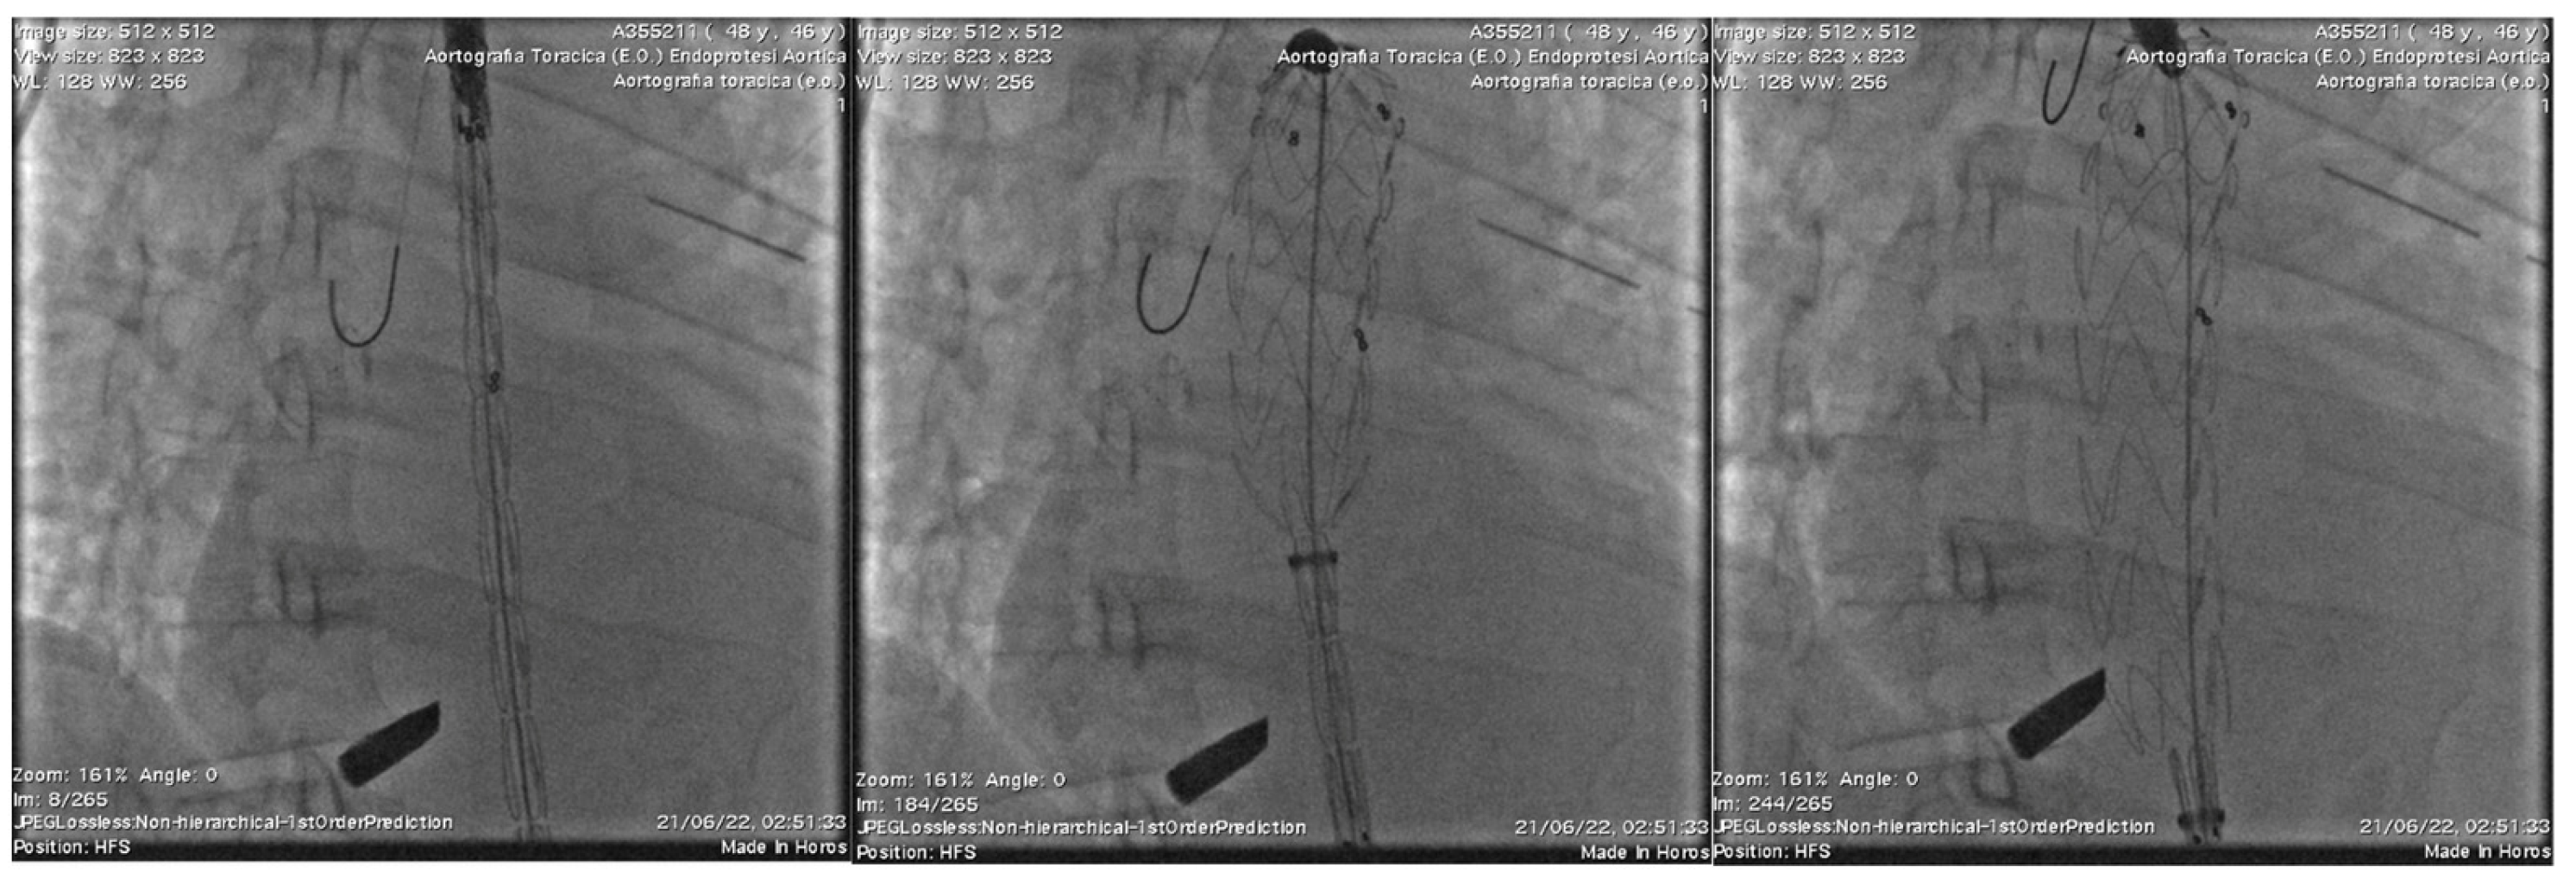

2. Case Presentation